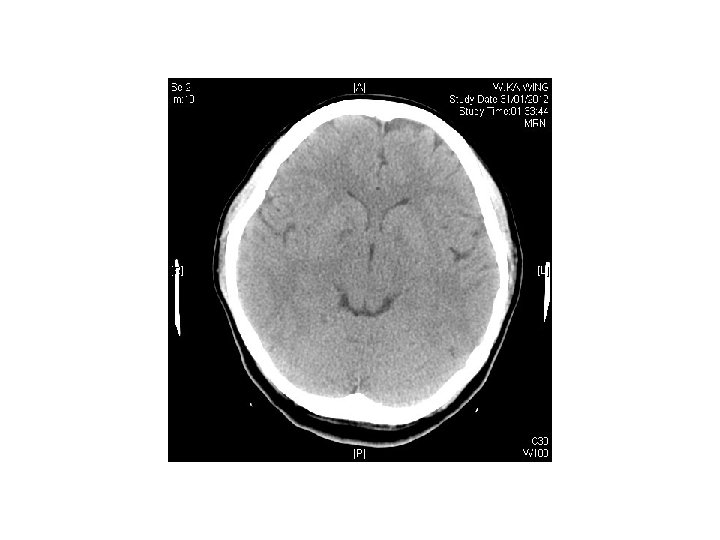

Case 5 • F/25 • She attempted suicide by burning charcoal at home • PE: GCS 14/15, BP 98/73 mm. Hg, Pulse 83/min, Sa. O 2 99% on 100%O 2 • Systems review were unremarkable. No focal neurological sign elicited.

Question • 1) describe the CT findings • 2) what is the diagnosis? • 3) what is the management?

Answers • Symmetrical hypodensity noted at bilateral basal ganglia • Compatible with CO poisoning • Rx : stabilize ABC • Administer 100%O 2 via tight fitting face mask • Intubate and provide IPPV on 100%O 2 if unconscious

• Record ECG, check ABG, COHB level • Consider hyperbaric oxygen therapy if • COHB >25%, pregnant patients with COHB >10%, myocardial ischemia, worsening symptoms despite oxygen therapy, all patients with syncope, neurological or cardiac abnormalities with elevated COHB